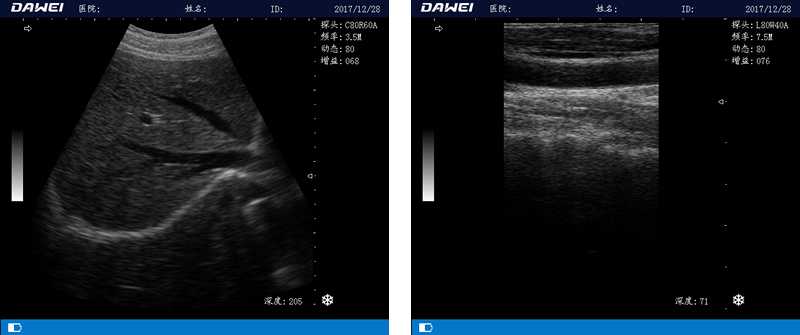

DW-580

筆記本全數(shù)字超聲診斷儀

1.優(yōu)質(zhì)的數(shù)字成像技術(shù),圖像更清晰